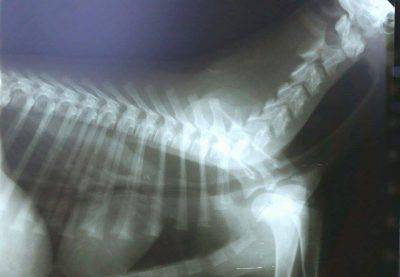

Diagnosi:

Per diagnosticare il Megaesofago, il veterinario effettua delle radiografie al cane previa assunzione di pasto barilato. Le razze che più ne soffrono sono in genere: il pastore tedesco, il golden retriever, i bulldog e a volte anche razze giganti come l’alano.